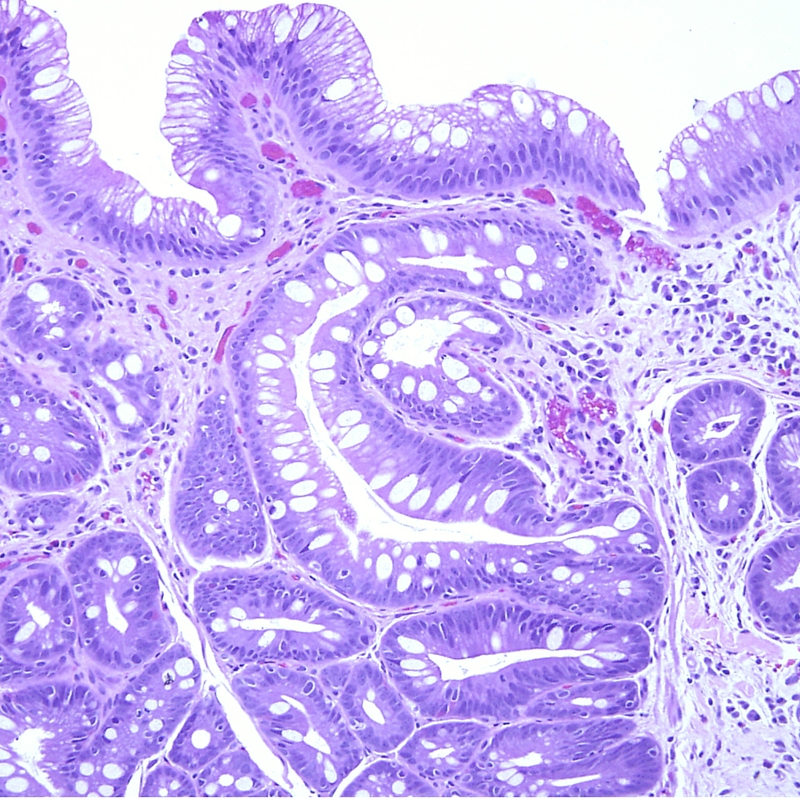

Read MoreThe grading system for prostate cancer is used to help assess the prognosis of prostate cancer. It also provides the doctor with the necessary information needed to select the most optimal treatment plan for the patient. Similar to staging prostate cancer, grade are given to each prostate cancer case to determine the severity of the disease. A urologist will assign a grade to the prostate cancer after the patient has undergone a prostate biopsy. The tissue samples are sent to a laboratory to be analyzed by a pathologist.